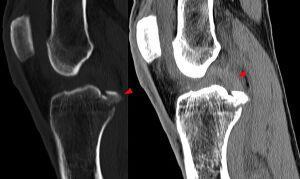

Röntgenbild: Kreuzbandriss - Hellerhoff commons.wikimedia.org, CC BY-SA 3.0

Bei einigen Komplettabrissen (zB Kreuzbänder oder Bandverletzungen in der Schulter) wird häufig operativ behandelt.